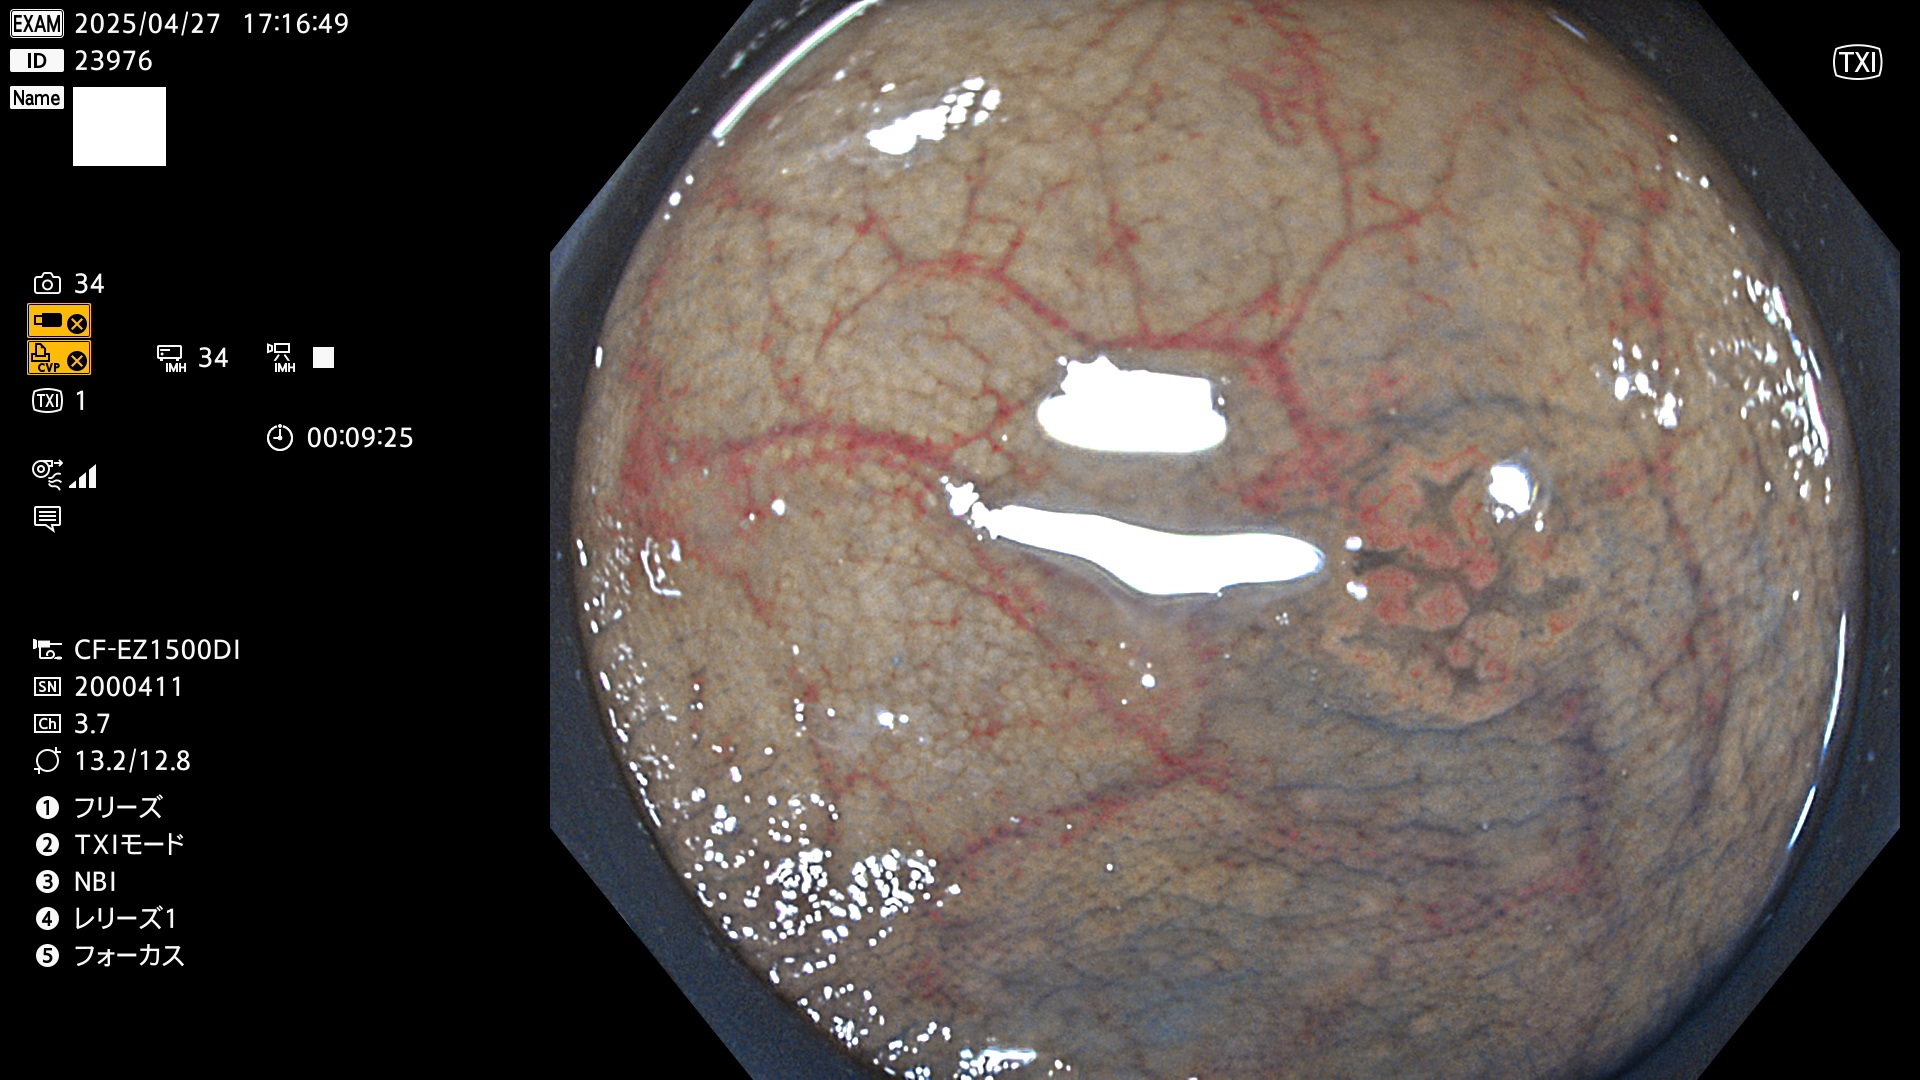

完全に平坦な物をUb、陥凹している物をUcと呼びます。Ubは認識が困難で、Ucはびらん(炎症)と紛らわしいために見落とされやすく、「内視鏡後・大腸癌」の原因になります。

抽出の対象期間 2025年4月24日〜4月27日の4日間(48件の検査)4個 (4/48=8%)